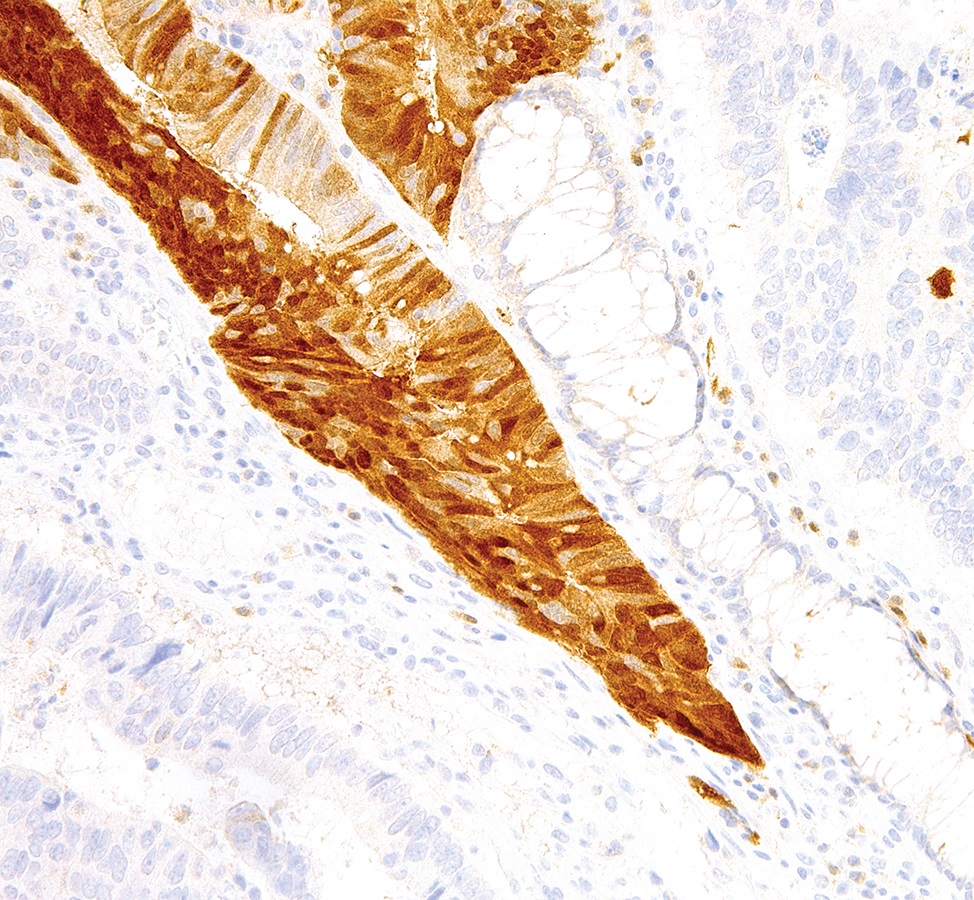

Arginase-1, encoded by the ARG1 gene, is a cytosolic metalloenzyme expressed predominantly in hepatocytes which plays a key role in the urea cycle by catalyzing the hydrolysis of arginine to ornithine and urea. Argininemia is an inherited autosomal recessive disorder characterized by a buildup of arginine and ammonia in the blood. Anti-Arginase-1 is highly specific for hepatocytes, and is therefore a sensitive and specific marker of benign and malignant hepatic tumors.